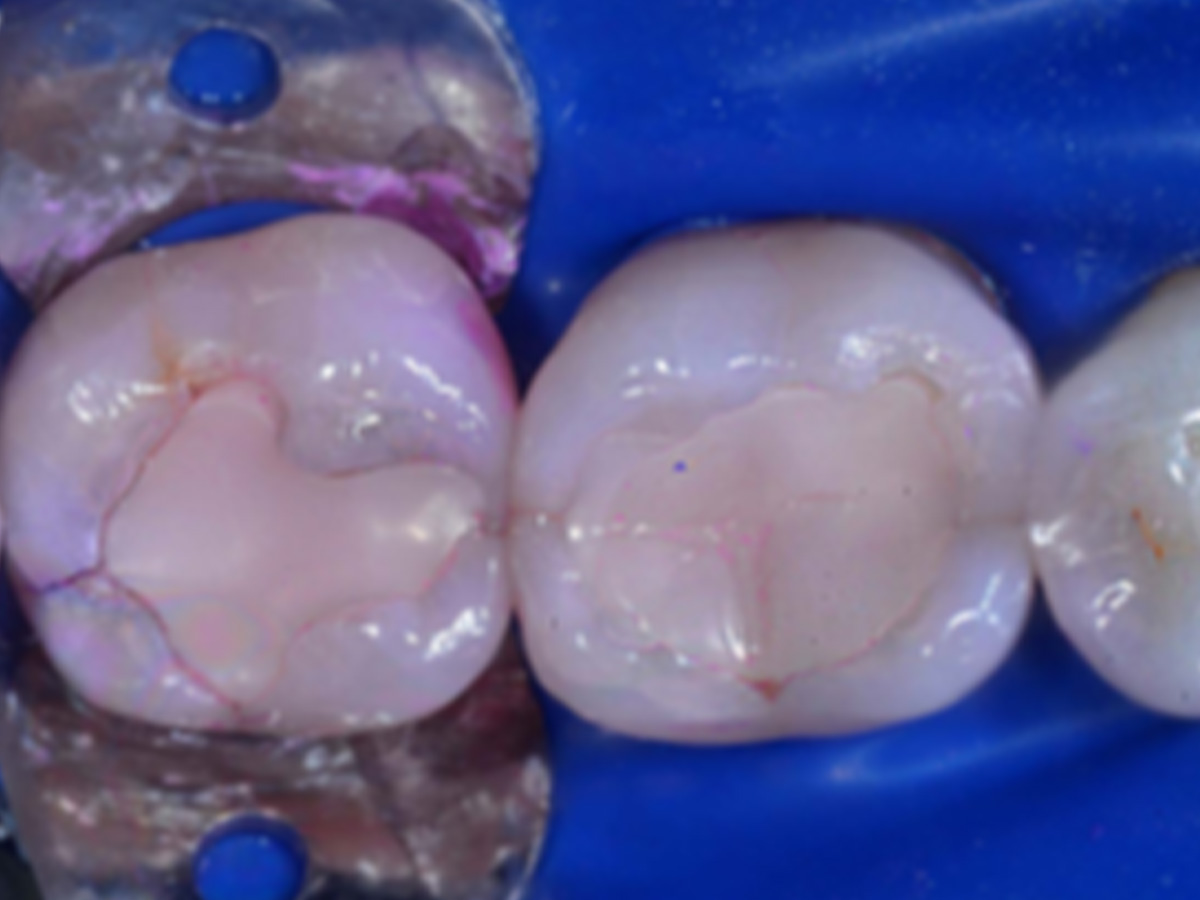

KURSINHALT

Die Herausforderungen in der direkten Kompositversorgung: Wie gelingt eine reproduzierbar perfekte Interdentalform ohne mühsame Nachbearbeitung? Wie lässt sich die Ästhetik im Frontzahnbereich mit minimalem Aufwand auf ein neues Niveau heben? In diesem praxisorientierten Kursformat lernen Sie die Injection-Molding-Technik kennen – eine effiziente Technik zur Umsetzung ästhetischer Frontzahn-Direktveneers und funktioneller Seitenzahnfüllungen mit minimalinvasivem Ansatz. Die speziell vorgeformten Matrizen überzeugen durch ihre hohe Passgenauigkeit sowie durch eine vielfältige Auswahl an Formen und Größen für die Front- und Seitenzahnbereiche. Die vollständig transluzenten Matrizen ermöglichen eine sauerstofffreie Aushärtung des Komposits – ohne Inhibitionsschicht, dafür mit einer perfekt glatten Oberfläche direkt nach der Polymerisation.

Vorteil:Eine zeitintensive Nachbearbeitung mit Schleifkörpern oder Polieren entfällt – das spart wertvolle Zeit und erhöht die Präzision und Qualität Ihrer restaurativen Versorgung.